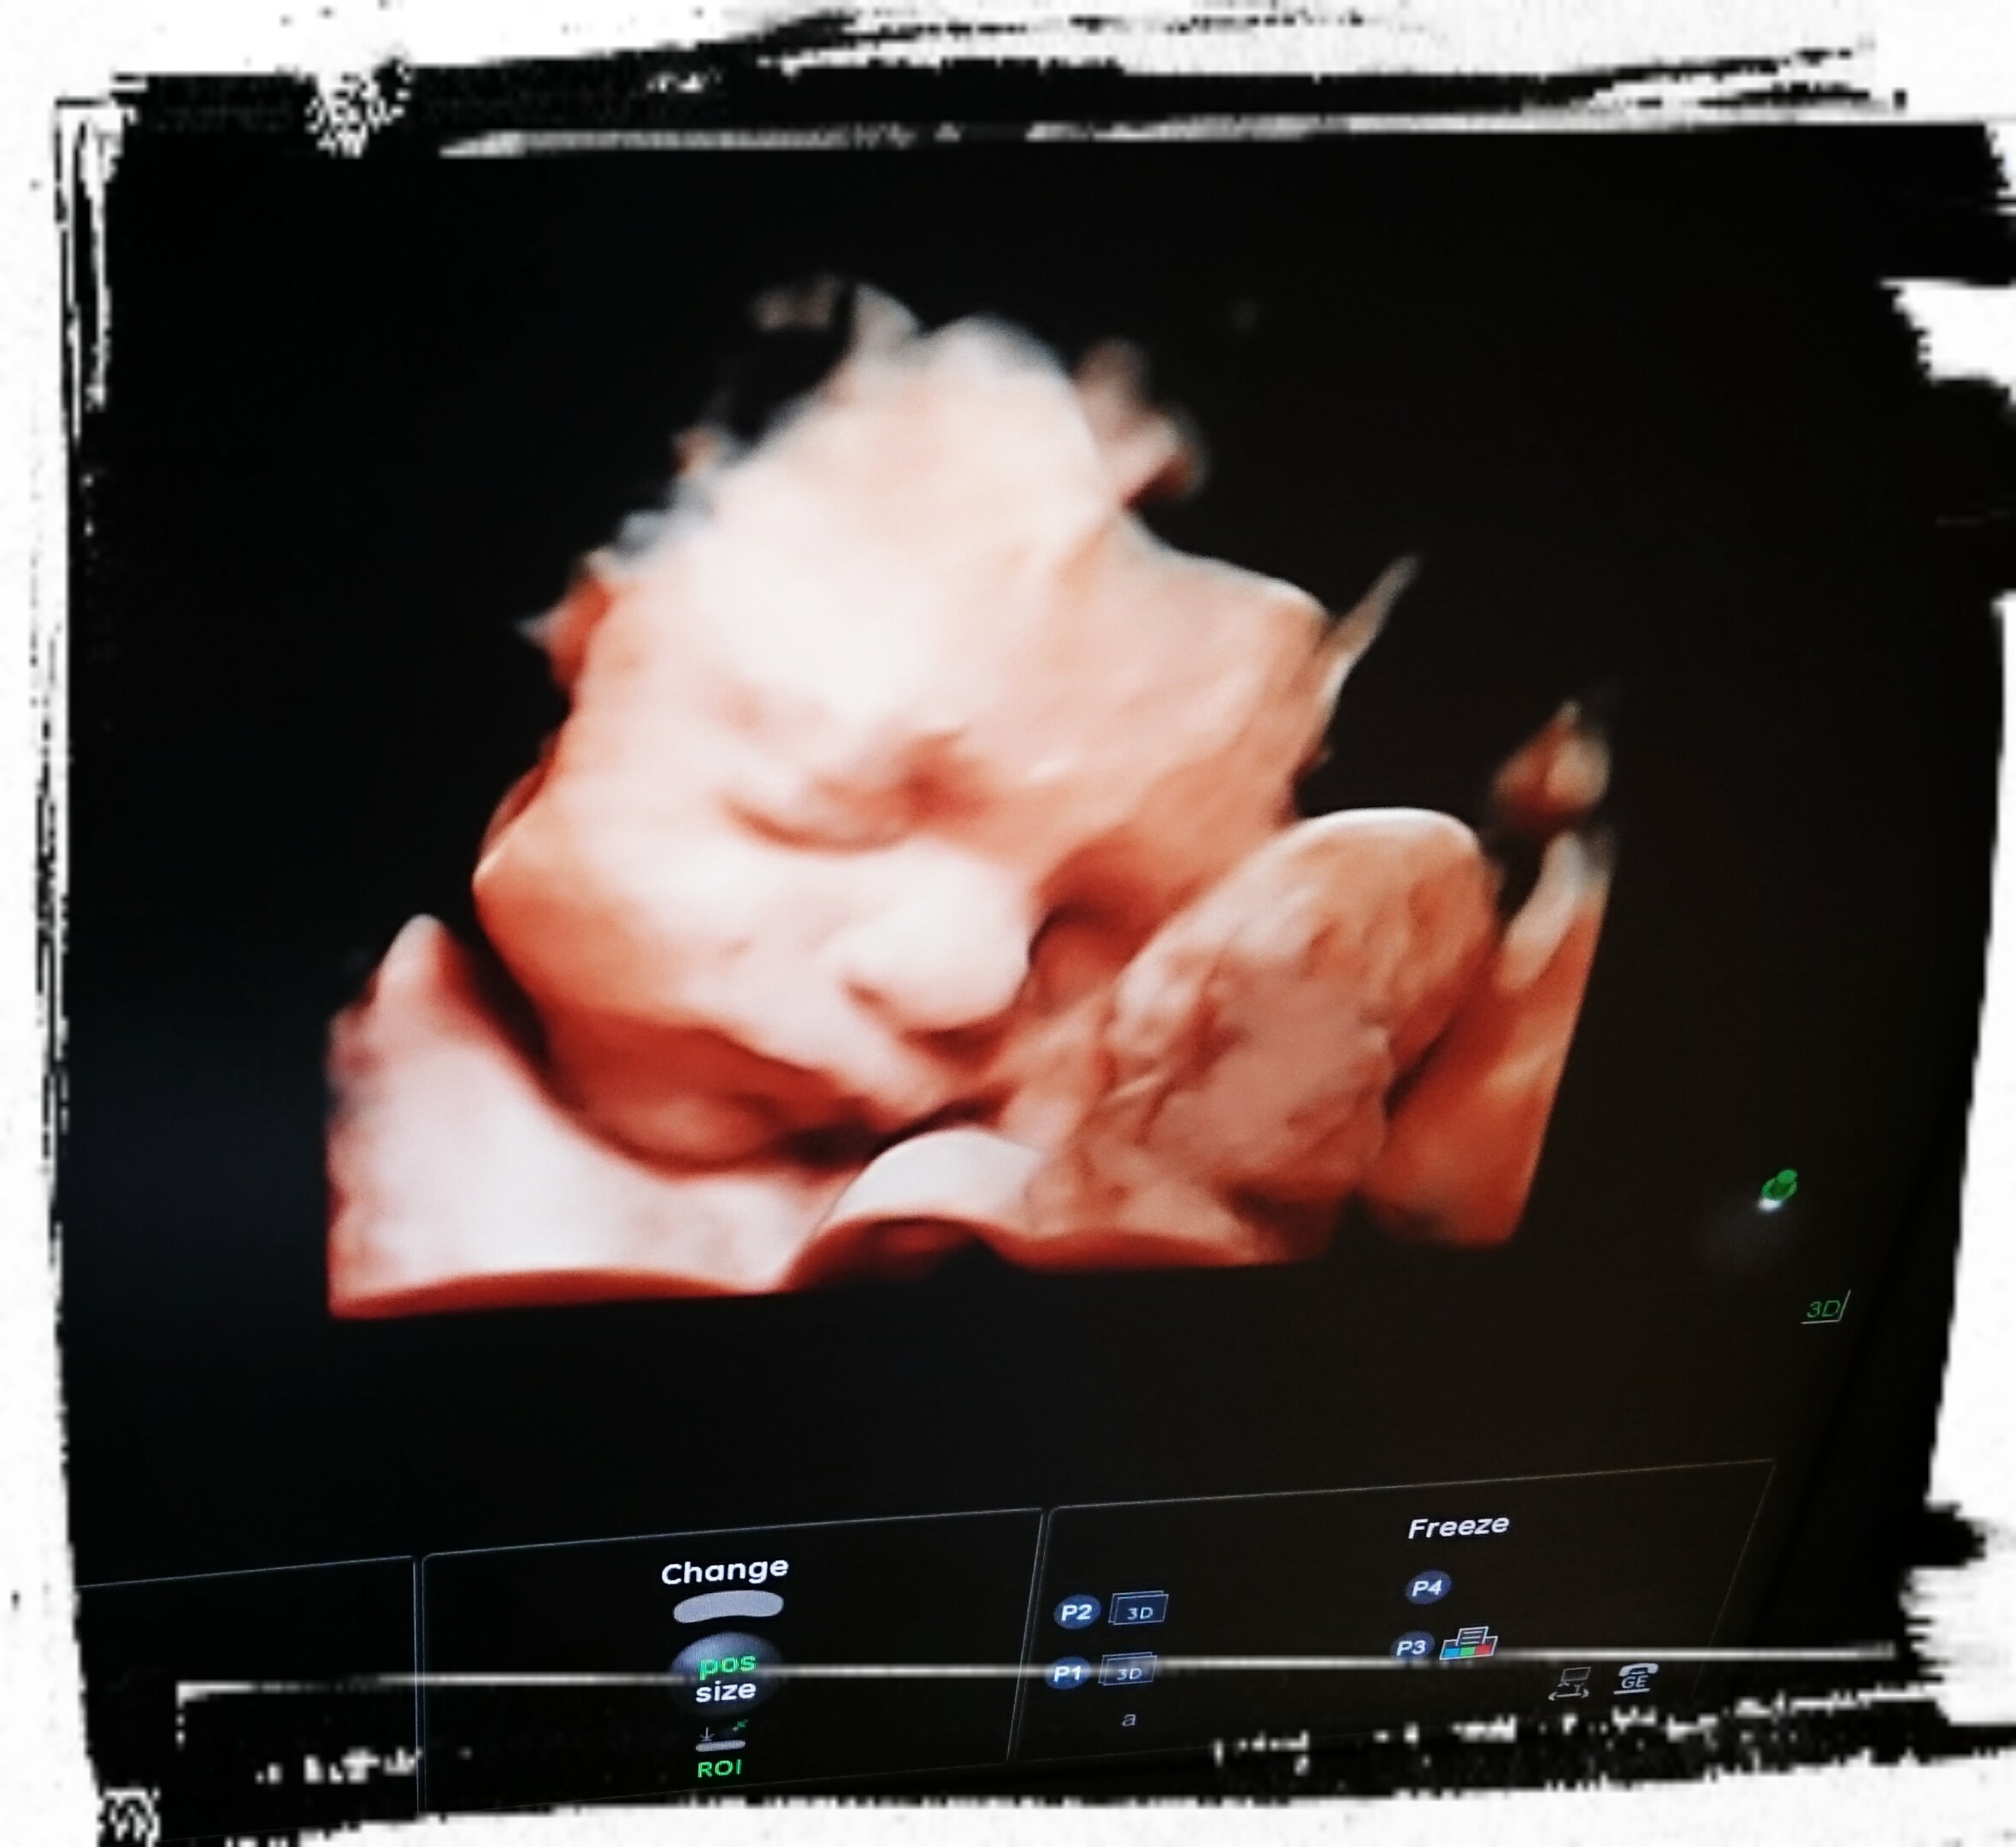

U nas wszystko ok zaczynamy 27 tc Julcia ma już 1kg, co jak co alemodeleczka z niej dobra, budzi mamę każdej nocy bo tak kopie lobuziakamała

kochamy ja ponad życie mimo że na razie tylko kopniaczki czujemy :* jest zdrowa i rośnie szybko, ułożenie ma glowkowe więc nastawiamy się na naturalny poród

staram się być bardo silna, dla Juleczki, ale nie mimo wszystko to jest dużo silniejsze odemnie.... Z szczęśliwej przyszłejmamusi nagle stałam się totalnie bezradnym człowiekiem niemogacympomoc rodzicom ;( to takie straszne uczucie.... Ale nie chce was przynudzac... Ważne że jakoś się trzymamy a mała rośnie mimo wszystko i jest zdrowiutka.... Dawno mnie tu nie było ale mąż mi zabrania korzystać z internetu bo czytam tylko o nowotworach i gorzej się doluje... Pozdrawiam buziaki dla was....pokażewam naszego cukiereczka jak mi sięuda wkleić zdjęcie